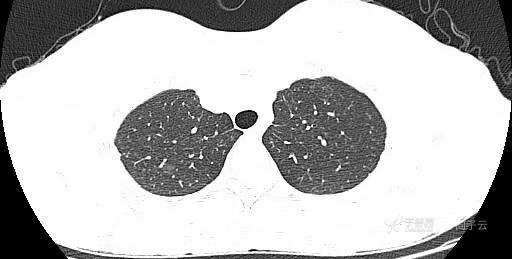

患者女,44岁,无特殊症状,做体检时发现右肺结节。查到1年前的体检CT片,右上肺当时就有一个直径约3mm的微小结节。两次检查检查图片如下:

以下9张为今年5.10的CT图片:

腺癌 (183)